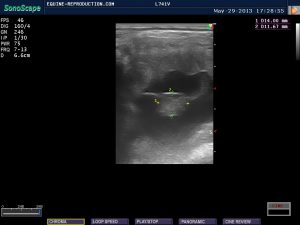

Normally, around day 20-21, when using standard ultrasound equipment, the “embryo proper”, as it is termed, will become visible as a small irregularity on the border of the vesicle – most commonly towards the ventral (bottom) region. With this particular ultrasound unit, which has images of superior quality, we can just see the embryo proper in the 19 day image above as a small whiter speck on the ventral region of the conceptus (arrowed in red below). By 20 day with this unit, it is very clearly visible in the image, albeit on the lower right margin of the vesicle rather than the more normal ventral region.

By day 22-23, again when using standard ultrasound equipment, the heartbeat should become visible, showing as a tiny flicker of grey-scale change. When using Color Doppler ultrasound, while the embryo itself may not be visible much earlier, the heartbeat can often be seen sooner, as evidenced by the 20 day CD video below which shows the brief flicker of color of the heartbeat.

The use of Color Doppler in the ultrasound indicates movement within the view. With the dual-color mode, two colors are seen – blue and orange – one indicating movement towards, the other movement away from the probe. What one is seeking is the movement of blood – blood flow. If however the mare herself moves, or the probe is moved within the mare, there is an artificial suggestion of movement evidenced by large areas of blue or orange. When seeking a heartbeat in an embryo, it is therefore imperative that the mare and the probe remain still. In the still CD 20-day image below, one can clearly see an orange speck within the embryo, which is indicative of a heartbeat. It is also visible as one quick orange flash at the beginning of the 20-day CD video. The embryonic heartbeat can be differentiated from the maternal blood flow in the surrounding vessels, as the former is significantly faster.